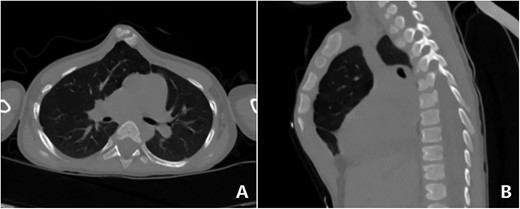

The patient was a 3-year-old boy. He was diagnosed with congenital ventricular septal defect shortly after birth, and he underwent heart surgery at the age of 1. The median sternotomy was used in the operation. After operation, the median part of the anterior chest wall is gradually protruded, whereas the bilateral parts of the chest wall are depressed. The deformity worsened with age. In order to correct the deformity, the child was admitted to our hospital at the age of 3. Physical examination showed that there was surgical scar on the anterior chest wall, the median part was protrusive and both lateral parts were obviously depressed (Fig. 1). No heart murmur was heard by auscultation. Imaging examination showed that the anterior chest wall was protrusive in the middle, with acute angle deformity on the top of the protrusion [3], and the lateral chest wall depressed on both sides (Figs 2 and 3). Echocardiography showed that the ventricular septum was integral without residual defect. The patient was diagnosed as secondary severe compound thoracic deformity before operation. After full preparation, the operation was performed under general anesthesia. Two incisions were made on both sides of the chest wall, respectively, with a length of 2 cm. The soft tissues and muscles were dissected to expose the ribs of the side chest wall. Two tunnels were made along the surface of the bone structures, from the incisions to the middle of the chest wall, and connected at the top of the protrusion, with an interval of 3 cm between the tunnels. Two steel bars were put into the tunnels, respectively. After compressing the protrusion with the middle part of the steel bar, two ends of the bar were fixed to two different ribs with steel wires. The interior fixation point was located at the rib of the depression, whereas the outside fixation point was located at the rib of the side chest wall (Fig. 4). After the drainage tube was placed in the operation field, the incision was closed, and the operation was completed. The operation was smooth without complications. The deformity disappeared after the operation (Fig. 5). A follow-up for 1 year showed that the appearance of chest wall was basically normal without obvious deformity (Fig. 6).

Three-dimensional examination. (A) Front view, (B) bottom view, (C) right side view and (D) left side view.